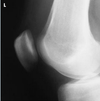

In the lateral projection of the ankle, the:

- talotibial joint is visualized

- talofigular joint is visualized

- tibia and fibula are superimposed

1 and 3 only